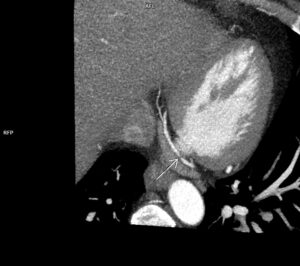

Figurile 9 si 10: reconstrucție multiplanară din examinarea recentă cu evidențierea stentului permeabil de la nivelul arterei circumflexe

Discuţie caz nr 114: Examinarea cardioCT are indicație de clasa 1 la pacienții cu sindroame coronariene cronice; la acest pacient se poate observă evoluția în dinamică a unor plăci de la nivelul arterei descendente anterioare – indicația de repetare a investigației s-a datorat faptului că pacientul acuză dureri de tip anginos nou apărute la 5 luni după coronarografia cu implantare de stent pe arteră circumflexă.